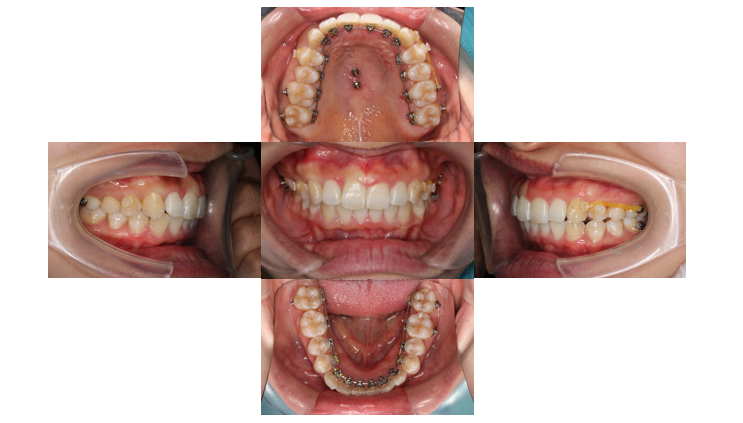

1年経過

歯と装置が当たらないようになったので青い材料を外します

右側から3番目の歯は他の歯と比べてねじれがある歯なのでゴムかけをして改善していきます